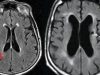

രോഗനിര്ണയം വൈകുന്നത് അപകടം; മുഴ കൂടാതെ സ്തനാര്ബുദത്തില് കാണുന്ന ലക്ഷണങ്ങളറിയാം

സ്ത്രീകളില് സ്തനാര്ബുദം വര്ധിച്ച് വരികയാണ്. പ്രത്യേകിച്ച് ചെറുപ്പക്കാരായ സ്ത്രീകളിലാണ് സ്തനാര്ബുദം വര്ധിച്ചുവരുന്നത്. എന്നാല് എന്തുകൊണ്ടാണ് സ്തനാര്ബുദം ബാധിക്കുന്ന സ്ത്രീകളുടെ എണ്ണം വര്ധിച്ചുവരുന്നതെന്ന കാര്യത്തില് ഇതുവരെ...